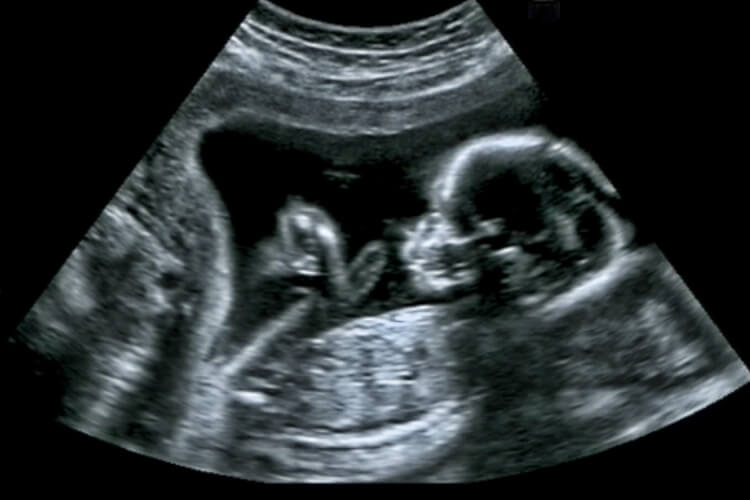

Zwei Wochen schwanger

Das erste, was Alhanna am nächsten Morgen tat, war, das Krankenhaus zu besuchen, um einen richtigen Test zu ertragen. Die Berichte stempeln auf den Schwangerschaftstest der letzten Nacht, Alhanna war in der Tat zwei Wochen schwanger. Mit den bestätigten Nachrichten planten Alhanna, Ricky zu überraschen. Laut ihr lieferte Keola diese gute Nachricht an sie und sie wird die beste Hilfe sein, um die Botschaft an Ricky zu liefern. Sie schrieb eine herzerwärmende Notiz und gebiete an Keolas Halsband und schickte sie nach Ricky, um die Bestätigungsnachrichten zu teilen. Was für ein erstaunlicher Moment muss es gewesen sein!

Ein Hundecode zum Entschlüsseln

Seltsamer und plötzlicher Schmerz

Alhanna Butlers Schwangerschaft ging bis in die 18. Woche reibungslos, als sie anfing, einen plötzlichen Schmerz in ihrem unteren Rücken zu spüren. Während ihrer Schwangerschaftszeit spürte sie das nicht vorher, in der Tatsache, dass sie während ihres Lebens noch nie einen solchen Schmerz hatte. Als ob dieser Schmerz nicht ausreicht, fühlte sie sich auch anfing, ein dringliches Gefühl in ihrem Bauch zu spüren.

Ricky wurde über die Gefahr der Mutter oder des Lebens des Kindes informiert. Nach mehreren Tests wurden die Ärzte endgültig sicher, dass sie den Zustand mit Ricky teilen. Sein Geliebte litt an einem sehr seltenen Zustand in den Nieren. Um zukünftige Tragödien zu verhindern, gab sie außerdem Alhanna im Krankenhaus für ein paar Tage zu.

Ein ungewöhnlicher Zustand

Die seltene Nierenerkrankung schadete Alhannas beide Nieren. Obwohl Infektionen der Harnwege während der Schwangerschaft üblich sind, sind Nierenerkrankungen überhaupt nicht üblich. Es war eine seltene Art von Bakterien, die gegen Antibiotika beständig ist. Diese Krankheit hätte bald neben ihren Nieren auf ihre anderen Organe verbreitet.